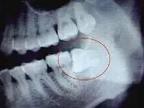

4.去骨

去除全部牙合面和部分頰側(cè)、遠(yuǎn)中的牙槽骨。一般原則:顯露牙冠最大周徑;盡量保持頰側(cè)皮質(zhì)骨高度;根據(jù)拔除難度及切割牙冠方式確定去骨量。為保持牙槽骨高度,頰側(cè)及遠(yuǎn)中去骨時(shí)可僅磨除貼近患牙的部分。為保護(hù)舌神經(jīng)、第二磨牙及其牙周骨質(zhì),原則上不去除舌側(cè)及近中牙槽骨,遠(yuǎn)中不超中線,將分離器置于遠(yuǎn)中骨板周圍進(jìn)行保護(hù)。

去骨時(shí)先確定最小的去骨量,一般垂直阻生去骨或增隙須達(dá)牙冠外形高點(diǎn)以下;水平和近中阻生應(yīng)達(dá)近中頰溝之下,以便分切牙冠;遠(yuǎn)中阻生至遠(yuǎn)中牙頸部以下,以便消除遠(yuǎn)中阻力。